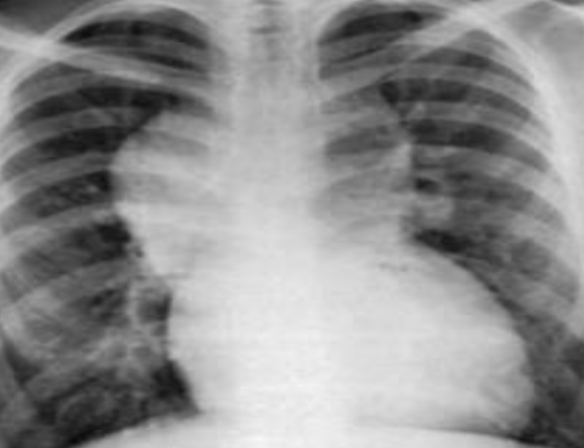

Case: Infant with Poor Weight Gain

- 9-month-old infant with poor weight gain, recurrent chest infection, and cardiac murmur

- Write 2 abnormalities in the X-ray

- Differential diagnosis

- More likely right-left shunt, boot-shaped heart

- TOF if cyanosis